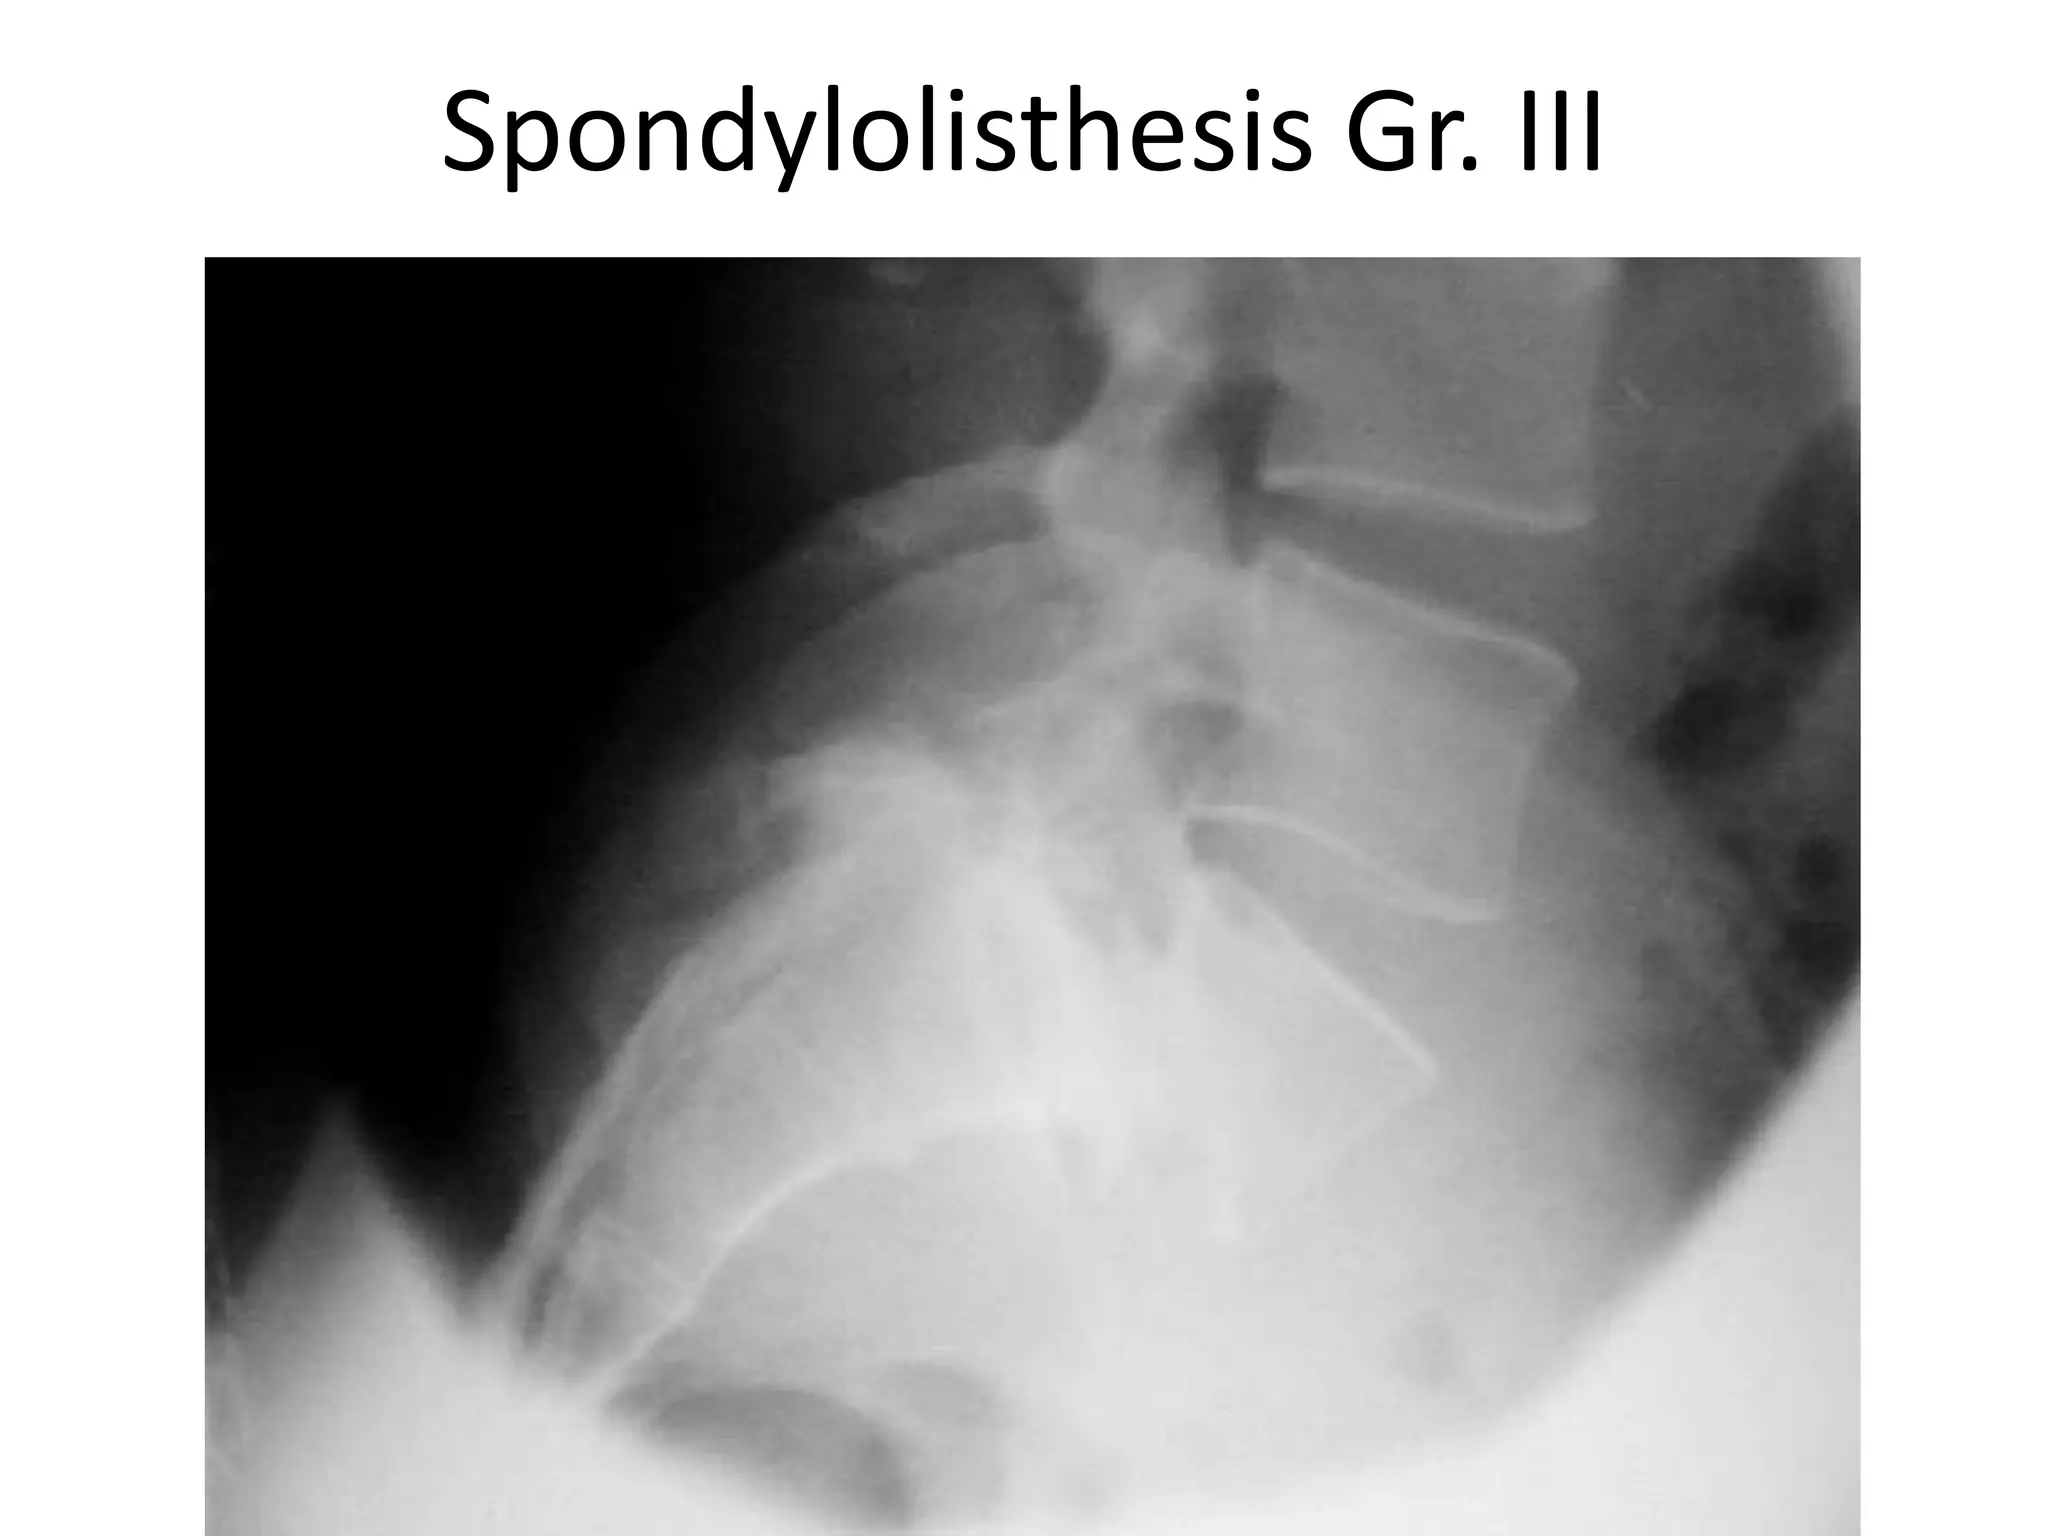

Spondylolisthesis Gr. III